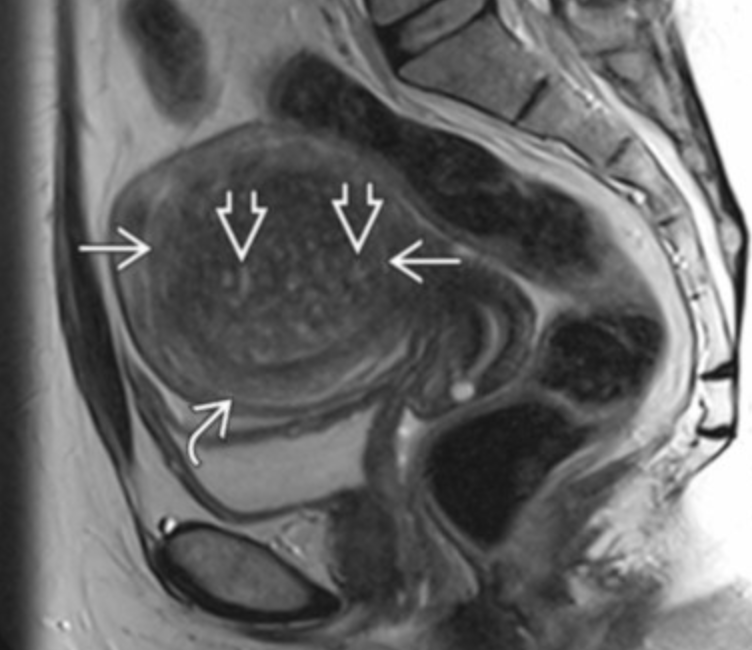

Junctional zone

• Arrow head = endometrium

• Middle arrow = junctional zone

• Long arrow = Outer myometrium